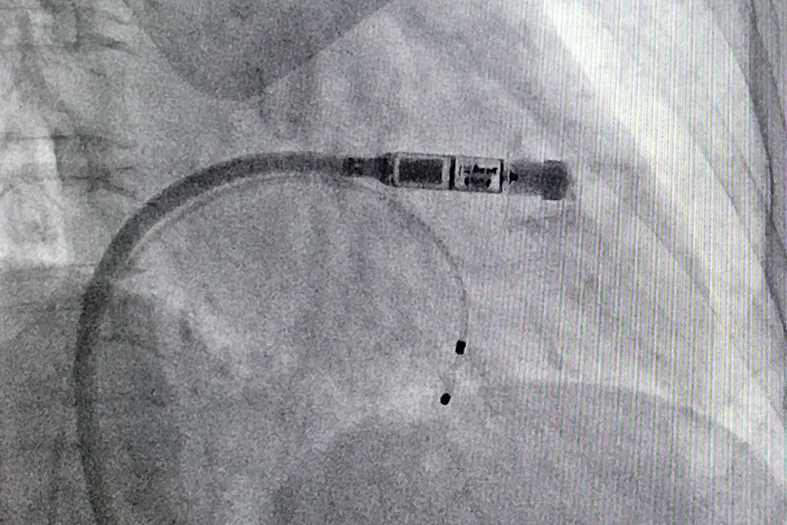

12月8日,山西省医院协会理事单位——运城市中心医院心血管内一科郝六一主任团队顺利完成晋南首例Micra AV双腔无导线起搏器植入手术。此举标志着该院心内科在心律失常诊治及起搏治疗领域迈入了精准治疗的新时代,实现了无导线起搏技术的新突破。

患者是名78岁的高龄女性,体形消瘦,既往因肺部疾病长期口服激素治疗,此次因反复头晕伴有晕厥入院,动态心电图提示患有III度房室传导阻滞,最慢心率为每分钟36次左右,符合永久起搏植入适应证。考虑患者高龄、身体状况等原因,郝六一团队经过反复讨论、充分与家属沟通后,为患者量身定制了手术方案,最终选择植入新一代Micra AV双腔无导线起搏器。12月8日,顺利完成植入,手术全程仅用时30分钟。术后起搏器各项参数测试良好,患者顺利返回病房,当天晚上即可下床正常活动。

此次植入的为新一代Micra AV双腔无导线起搏器,不仅继承了第一代无导线起搏器的所有优点,如体积仅有维生素胶囊大小,重量仅2克,兼容1.5 T/3.0 T全身核磁共振扫描检查,同时通过算法革新,能够感知心房信号起搏心室,实现生理性的房室顺序起搏,改善患者的心功能。Micra AV无导线起搏器能够为更多心动过缓患者(如房室传导阻滞患者)上一层“保护器”。(武金娥)